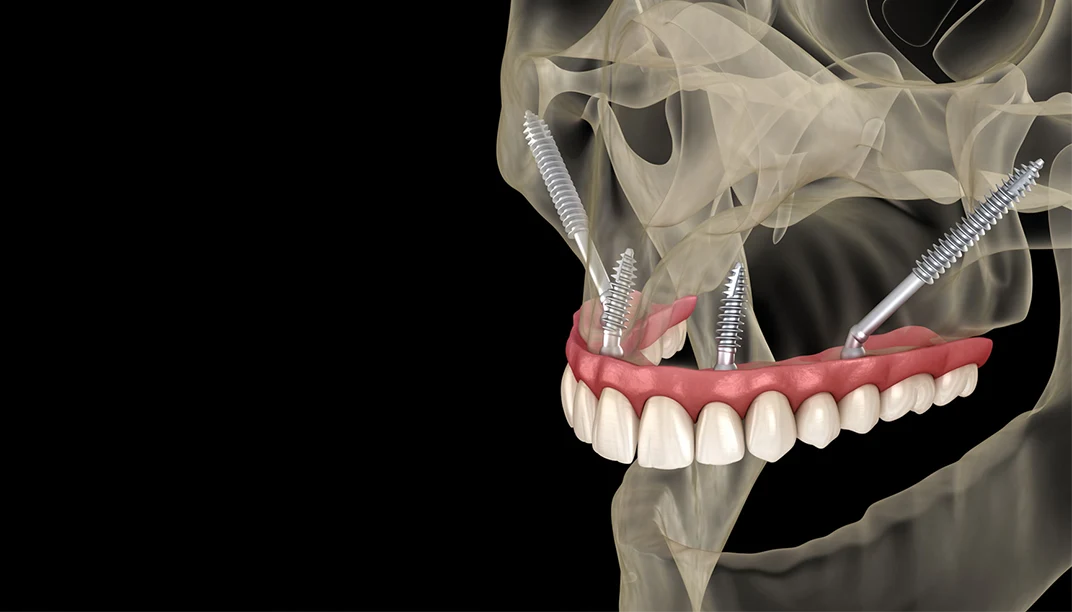

تعد زراعه الاسنان المصغره زراعه التريجويد من أحدث التقنيات المتقدمة في عالم زراعة الأسنان، حيث تعتمد على حلول فورية وفعالة لتعويض الأسنان المفقودة بطريقة آمنة وسريعة.

تتميز زراعة الأسنان المصغرة بأنها أقل تدخل جراحي من الزراعة التقليدية، وتناسب الحالات التي تعاني من ضعف كثافة عظام الفك، بينما تعد زراعة التريجويد الحل الأمثل للمرضى الذين يعانون من تآكل شديد في عظام الفك العلوي.

خطوات زراعة التريجويد

تعتبر خطوات زراعه الاسنان المصغره زراعه التريجويد من أكثر الإجراءات دقة وتتم عبر:

- الفحص بالأشعة المقطعية لتحديد مكان العظم بدقة.

- تجهيز الموقع المناسب خلف الفك العلوي.

- تثبيت الزرعة في عظم التريجويد بزاوية دقيقة.

- تركيب الدعامة والتاج المناسب بعد الالتئام.

زراعة التريجويد للأسنان المفقودة

تعد زراعة التريجويد للأسنان المفقودة أحد أفضل الحلول الحديثة لتعويض الأسنان في الجزء الخلفي من الفك العلوي عندما لا تتوفر كثافة عظمية كافية وتتميز هذه التقنية بأنها تعتمد على عظام التريجويد القوية خلف الفك، مما يجعلها بديل مميز لعمليات رفع الجيب الأنفي أو زراعة العظم التقليدية.

نجاح زراعة التريجويد

يرتبط نجاح زراعه الاسنان المصغره زراعه التريجويد بعدة عوامل أهمها خبرة الطبيب، وجودة الأشعة ثلاثية الأبعاد المستخدمة في التخطيط، وحالة العظام لدى المريض وتحقق هذه التقنية نسب نجاح عالية جدا نظرا لاعتمادها على عظام قوية ومستقرة بطبيعتها كما أن الزراعة تكون أطول قليلا من الزراعة التقليدية، مما يمنحها ثبات أفضل وقدرة على تحمل قوى المضغ العالية ومع العناية المناسبة والمتابعة الدورية يمكن أن تستمر نتائجها لعقود.

ما هي زراعة التريجويد؟

زراعة التريجويد هي نوع متقدم من زراعة الأسنان يعتمد على زرع الدعامة في عظم التريجويد القوي خلف الفك العلوي.